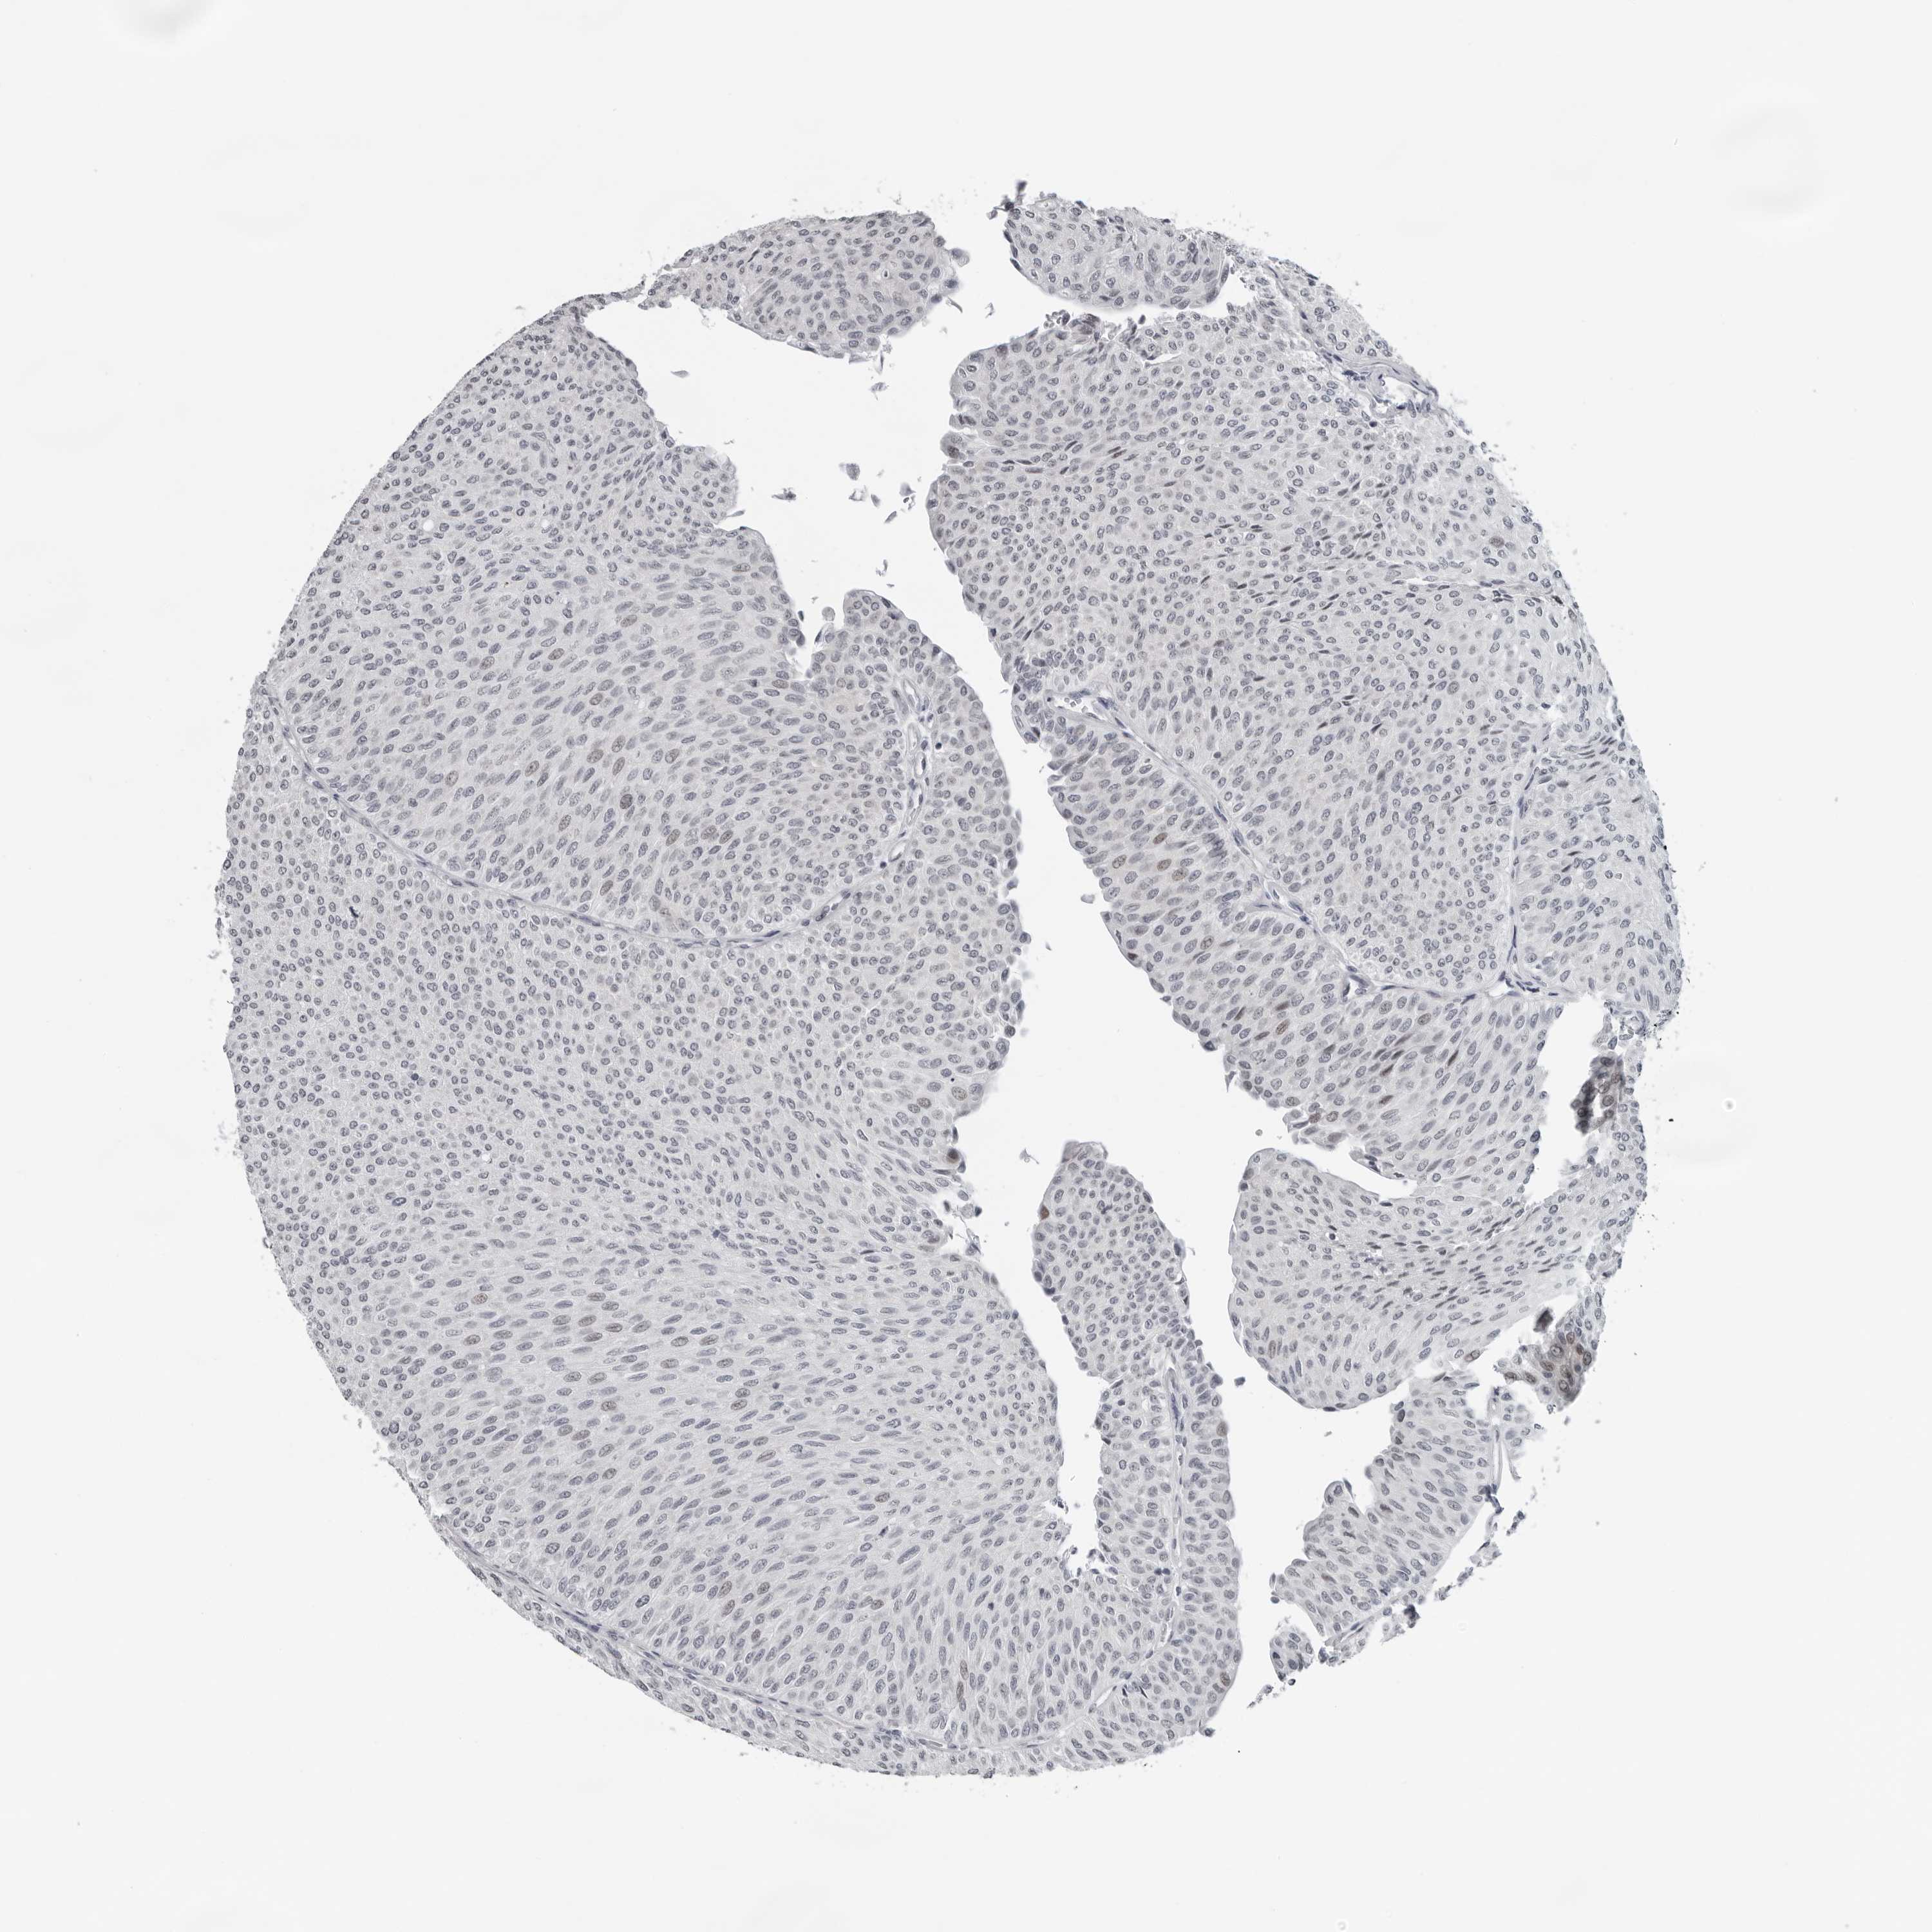

UROTHELIAL CANCER - Protein expressioni

A mouse-over function shows sample information and annotation data. Click on an image to view it in a full screen mode. Samples can be filtered based on level of antibody staining by selecting one or several of the following categories: high, medium, low and not detected. The assay and annotation is described here.

Note that samples used for immunohistochemistry by the Human Protein Atlas do not correspond to samples in the TCGA dataset.

Antibody stainingi

Antibody staining in the annotated cell types in the current human tissue is reported as not detected, low, medium, or high, based on conventional immunohistochemistry profiling in selected tissues. This score is based on the combination of the staining intensity and fraction of stained cells.

Each image is clickable and will lead to virtual microscopy that enables deeper exploration of all samples and also displays staining intensity scores, fraction scores and subcellular localization as well as patient and tissue information for each sample.

Antibody HPA024313

Antibody HPA027983

Antibody HPA028628

Urothelial carcinoma, Low grade